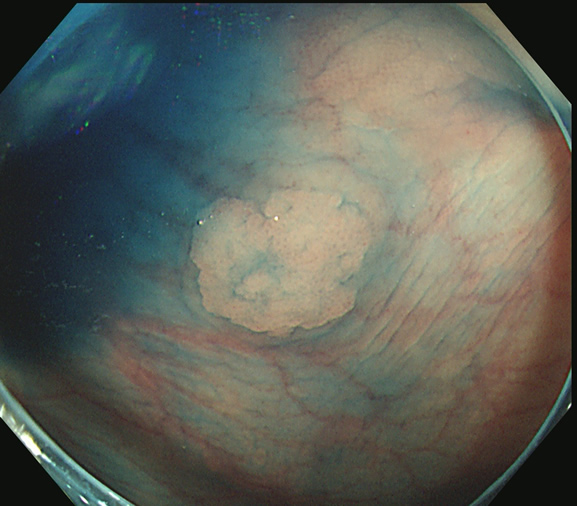

色素(インジゴ・カルミン)散布

青い色素(インジゴ・カルミン)を散布すると平坦で解りにくい病変が明瞭になり発見し易くなります。

しかし、コツがあります。大量に撒きすぎると「青い液の溜まり」ができて、かえって死角を作ります。粘膜の表面に薄く、塗る位が適量です